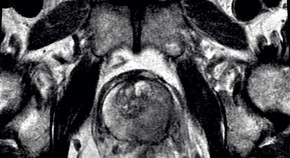

• 2018 has been an exciting year for imaging in urology, especially in the field of prostate cancer. In this context, multiparametric MRI and molecular imaging targeting prostate-specific membrane antigen provide practice-changing developments for detection and diagnostic work-up.

• In the past year, the results of three studies in the field of prostate cancer imaging — the prostate MR imaging study (PROMIS), an analysis of the cost-effectiveness of various diagnostic strategies based on PROMIS data, and a retrospective analysis of a prostate-specific membrane antigen (PSMA)-directed PET radiopharmaceutical — have been published that could have lasting effects on clinical practice.